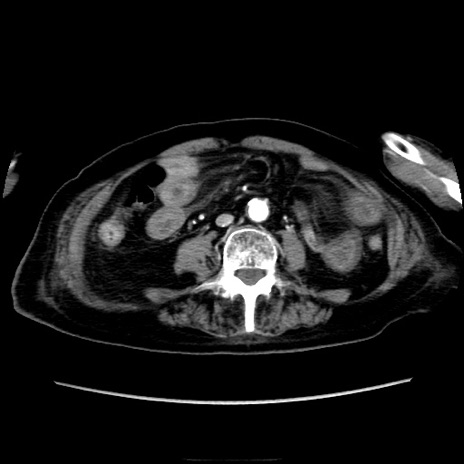

症例40(横断像)

【症例】90歳代女性

【主訴】腹痛・嘔吐

【現病歴】 食欲低下、嘔吐があり昨日他院受診。肺炎と診断され入院となる。入院後より腹部全体に圧痛あり。胃管留置され経過みていたが、症状持続するため、

当院転院となる。

【既往歴】胸椎圧迫骨折、胆石症

【身体所見】腹部:中央に激痛あり、圧痛あり、反跳痛不明

【データ】WBC 17100、CRP 18.82

横断像